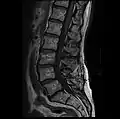

- MRI lumbar spine with degeneration, post-hemilaminectomy L4-5 (sagittal T2 FRFSE)

- MRI lumbar spine with degeneration, post-hemilaminectomy L4-5 (sagittal T1 FSE)

- MRI lumbar spine with degeneration, post-hemilaminectomy L4-5 (sagittal FAST STIR)

- MRI lumbar spine post-hemilaminectomy (sagittal T2 FRFSE)

- MRI lumbar spine post-hemilaminectomy (sagittal T1 FSE)

- Contrast MRI lumbar spine post-hemilaminectomy (sagittal T1 FSE FS)

- MRI lumbar spine pre-hemilaminectomy (sagittal T2 FRFSE)

- MRI lumbar spine pre-hemilaminectomy (sagittal T1 FSE)

- MRI lumbar spine pre-hemilaminectomy (sagittal FAST STIR)